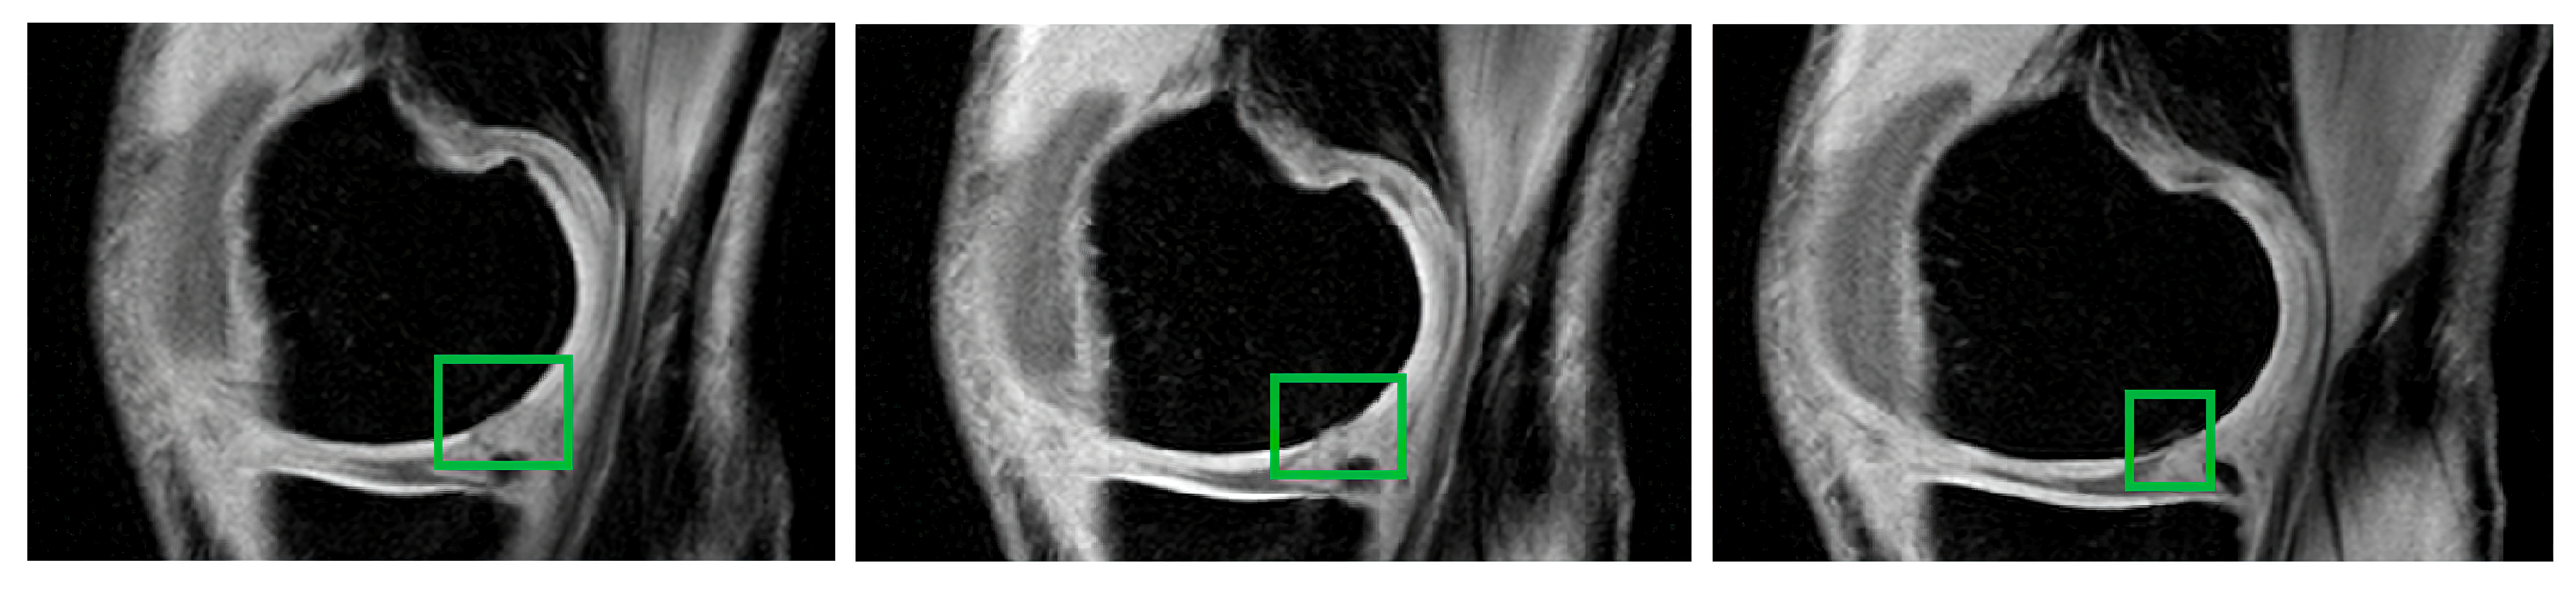

We use data from three variable MR sequences for the testing of the segmentation performance of cartilage modeling: proton density-weighted images, gradient echo images, and T2-weighted images. The provided testing is further based on 1500 images in total from these datasets. All the images used are from the public database, Osteoarthritis Initiative (OAI) [52]. In Figure 2, we present an example of individual datasets used in this study.

Figure 2. Examples of knee MR images used in this study, from left: T2-weighted image, proton density-weighted image, and gradient echo image.

The MR sequence based on proton density-weighted imaging is capable of recognizing the contrast between cartilage defects and abnormal cartilage composition. The further benefit of this imaging is the contrast recognition of the cartilage morphology and other tissues such as menisci and ligaments. For these reasons, this sequence is substantially important for clinical practice in the investigation of early cartilage loss, where only tiny contrast changes in the cartilage structure are notable. Thus, we mainly use the data from this sequence for the classification of cartilage loss, as we describe further. In Figure 3, we provide examples of three images of articular cartilage that contain early signs of osteoarthritis loss. This disorder is manifested as a variation of the MR signal in the form of lower image intensity in the spots (green squares) where the cartilage is missing.

Figure 3. Examples of three images of the RoI of the articular cartilage area where cartilage is missing (green squares) as a result of the early signs of osteoarthritis.